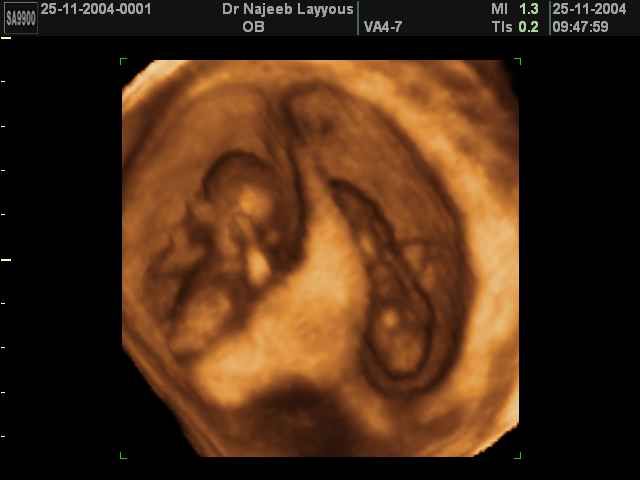

- 3D Photos échographie de grossesse multiple

3D Photos échographie de grossesse multiple : Jumeaux, triplés et quadruples| Dr N Layyous